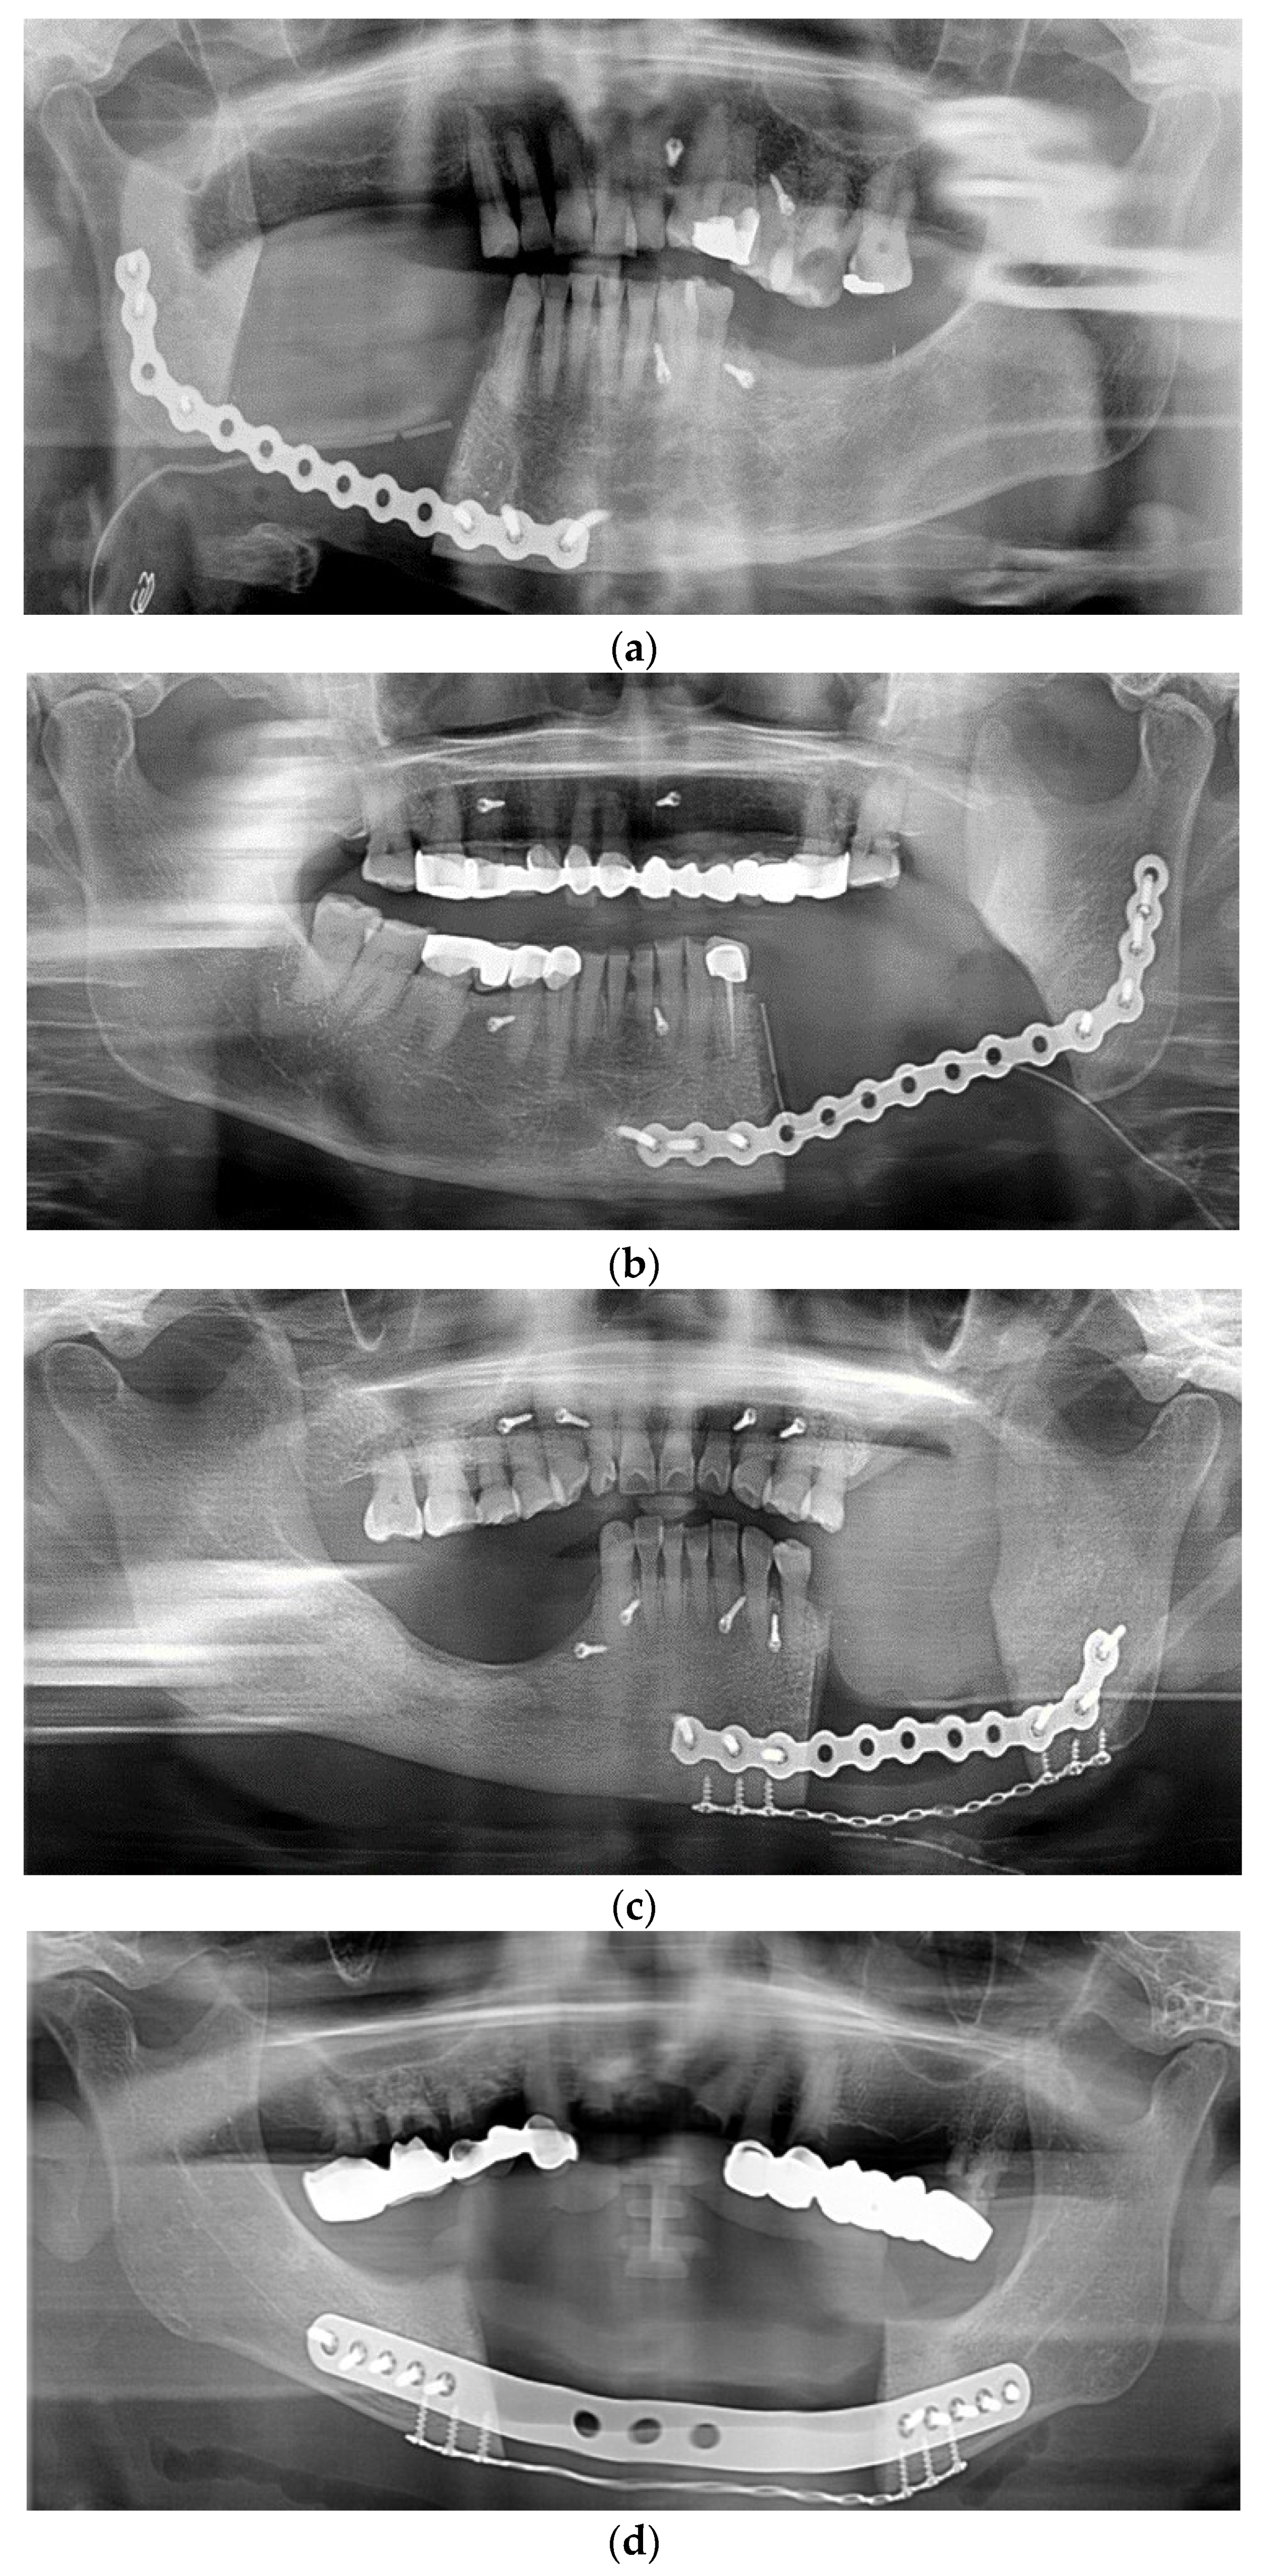

Spontaneous Osteogenic Potential of Periosteum after Segmental Mandibulectomy in Patients with Medication-Related Osteonecrosis of the Jaw (MRONJ): A Retrospective Study of 14 Cases

3. Results